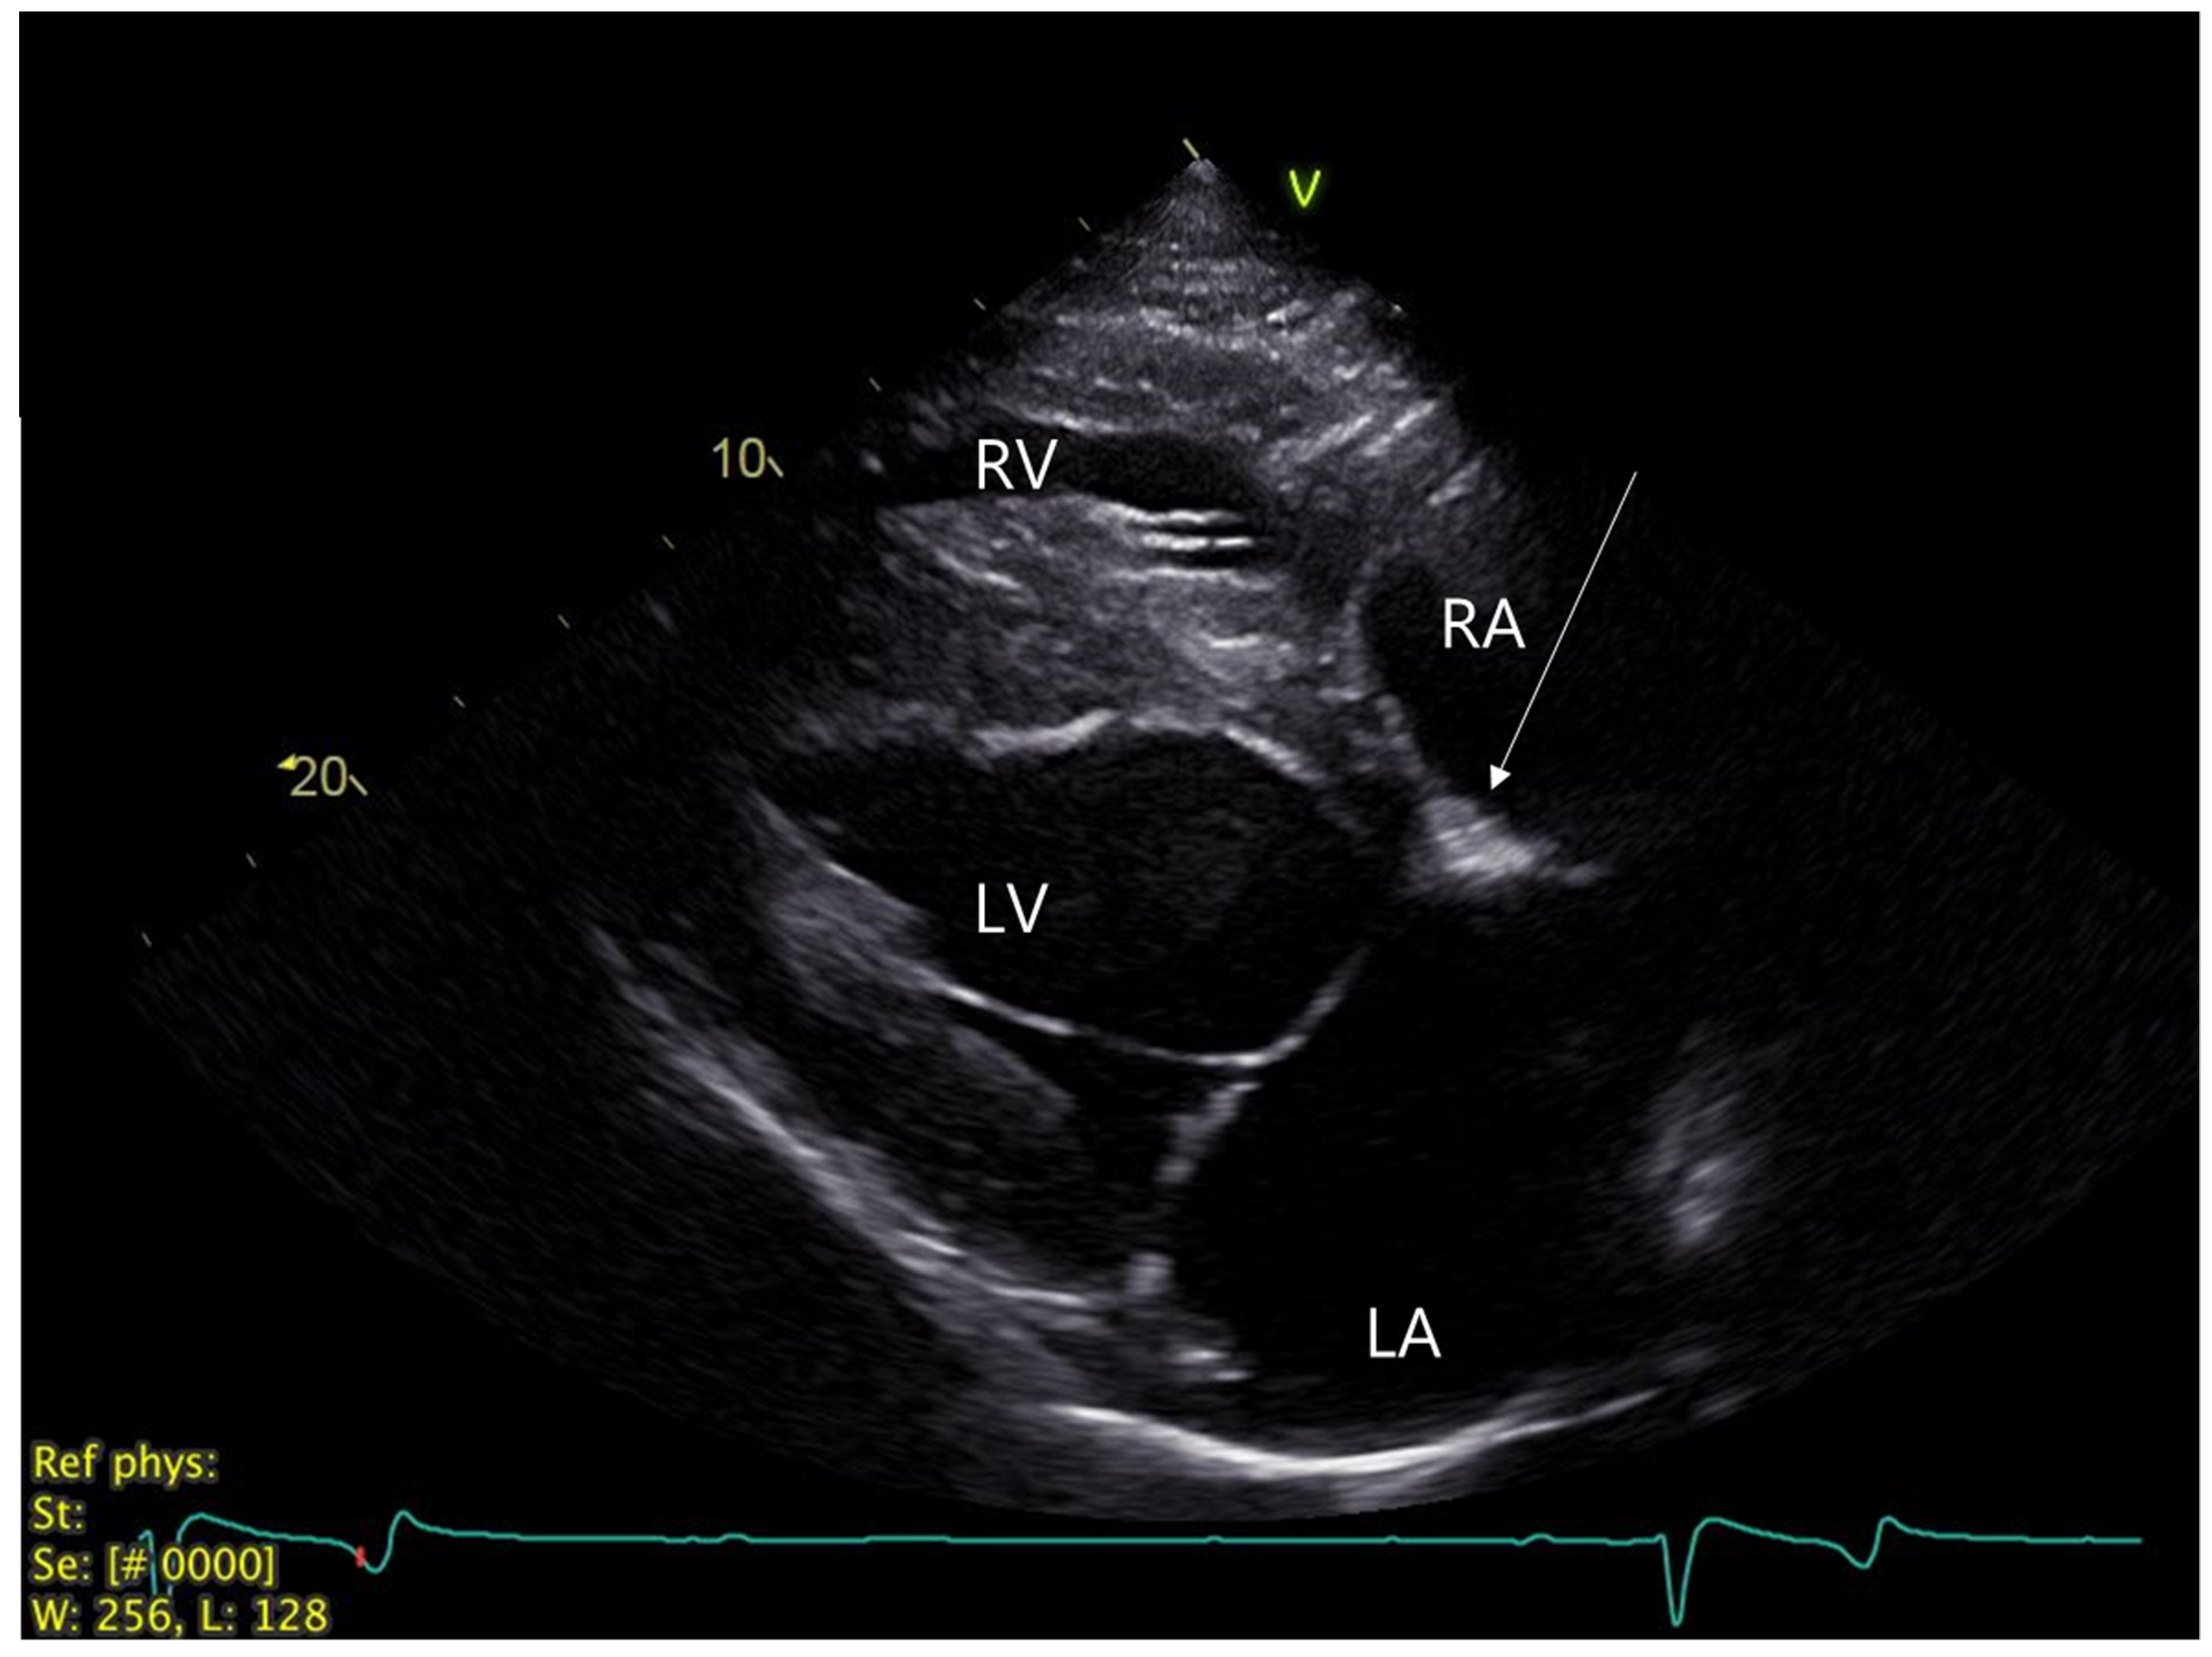

2.1. Clinical Investigation at Referral Center